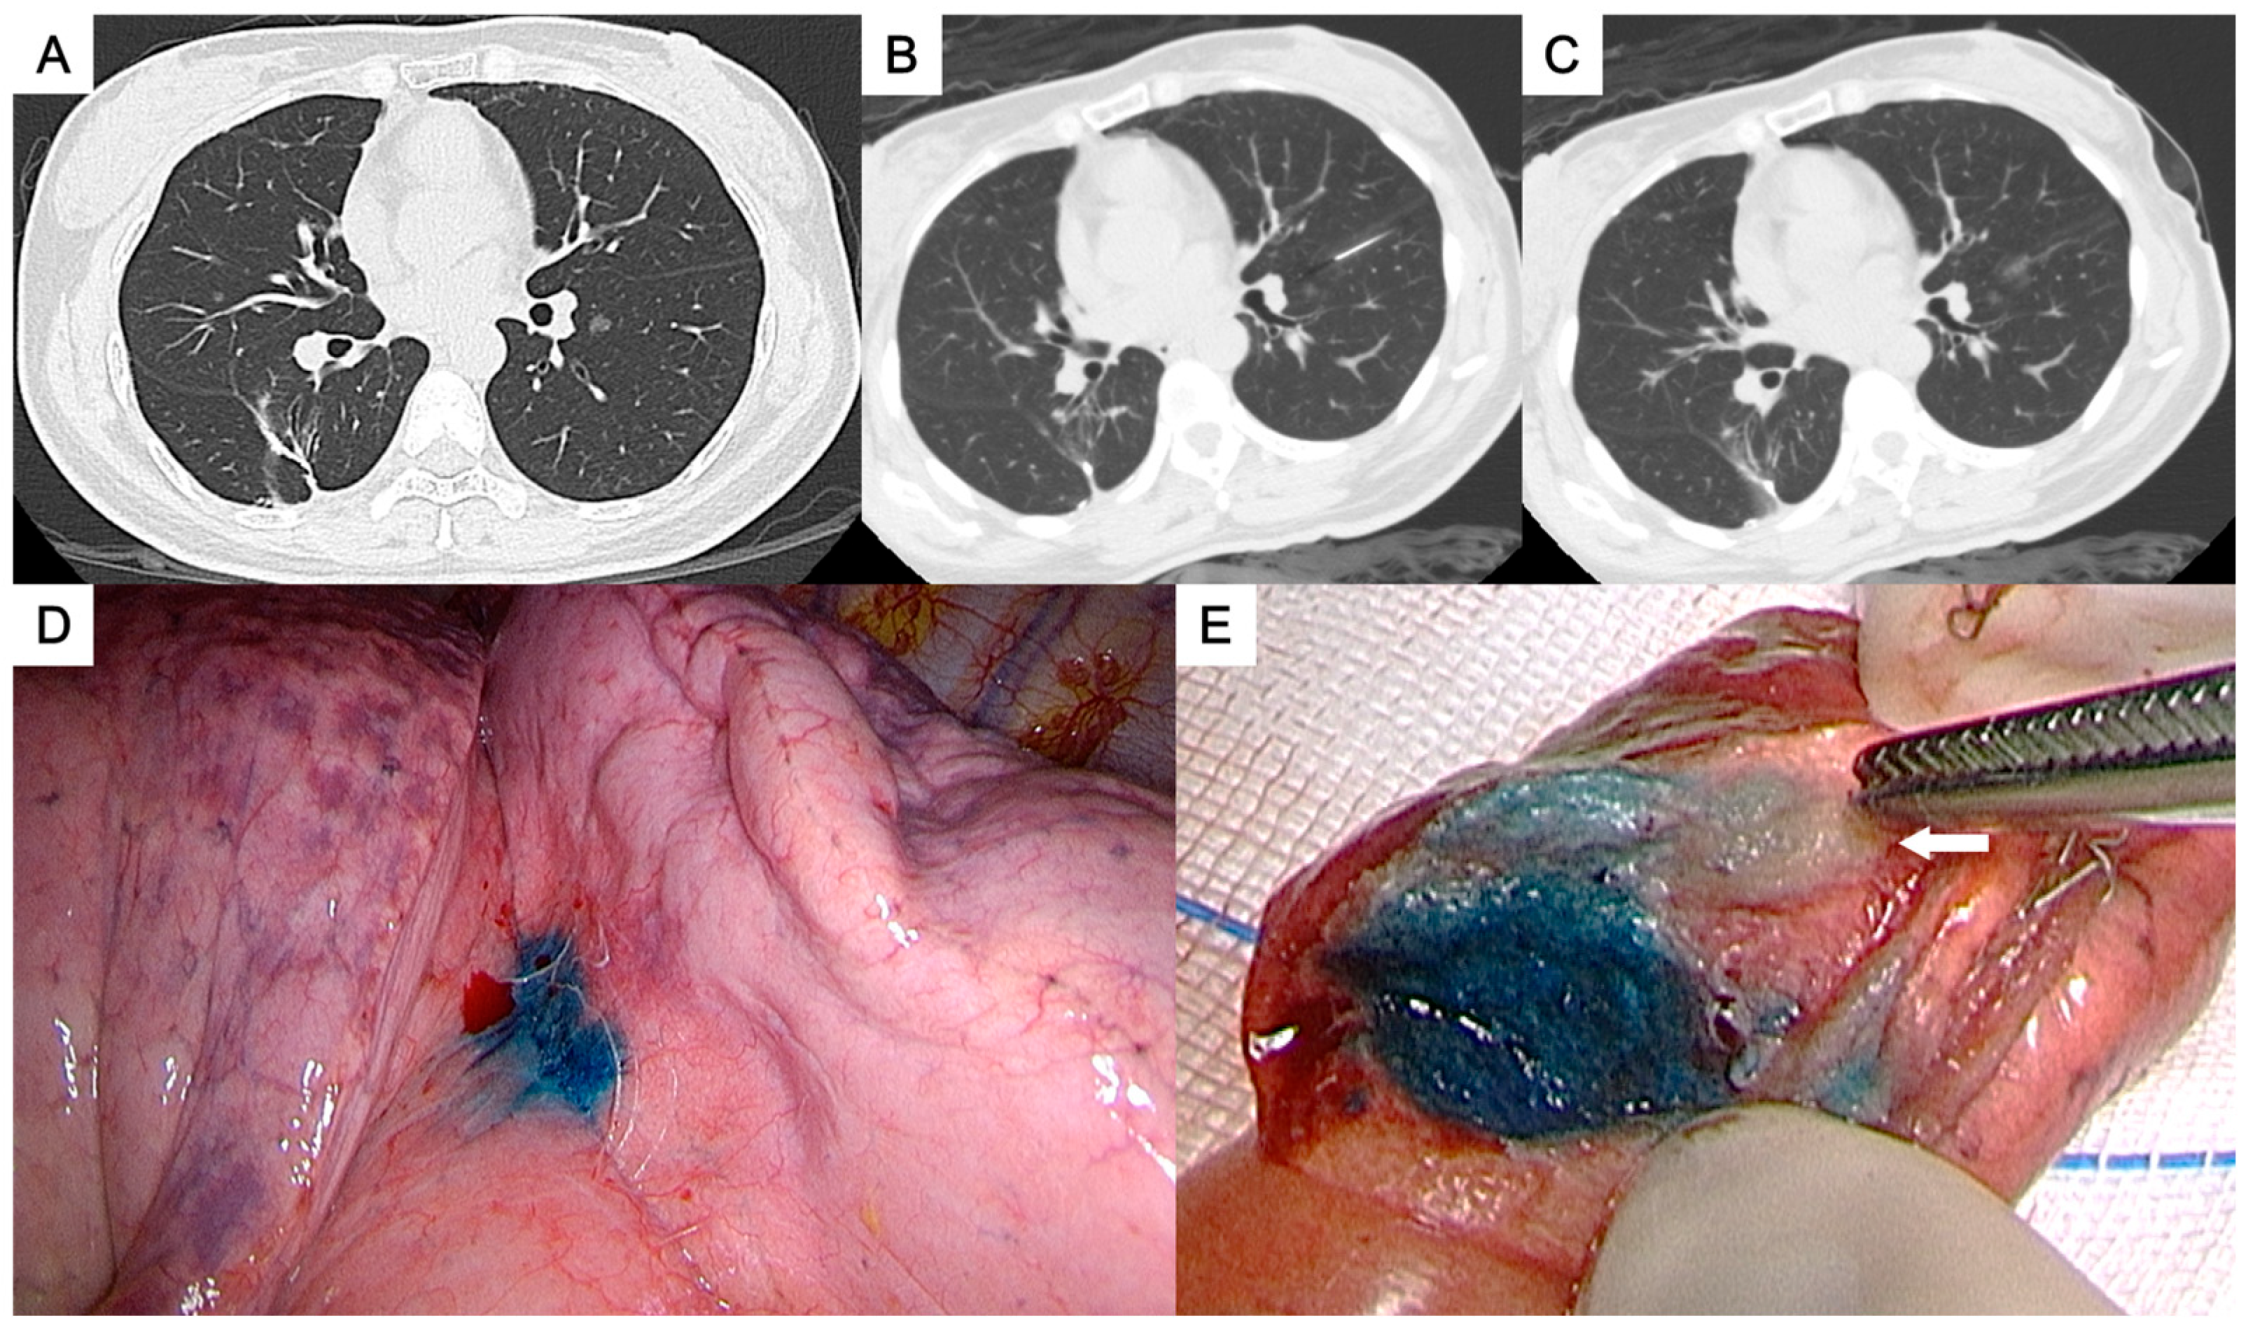

Figure 1. (A) A ground-glass nodule in the left lower lobe near the interlobar fissure. (B, C) Patent blue dye was injected into the subpleural area adjacent to the nodule. (D) Successful localization with a visibly stained area on the visceral pleura. (E) The tumor (arrow) was clearly identified in the resected specimen. The pathological result was adenocarcinoma.

• For the perifissural nodules (Figure 1), we introduced the needle by the shortest way from the chest wall to the nodule and injected the PBD in the subpleural area. There is an alternative transfissural approach (Figure 2) to avoid pulmonary vessels, scapula, and ribs, with the dye retention in the subpleural area.

• Perifissural nodules: nodules close to the interlobar fissure (Figure 1 and Figure 2) ;